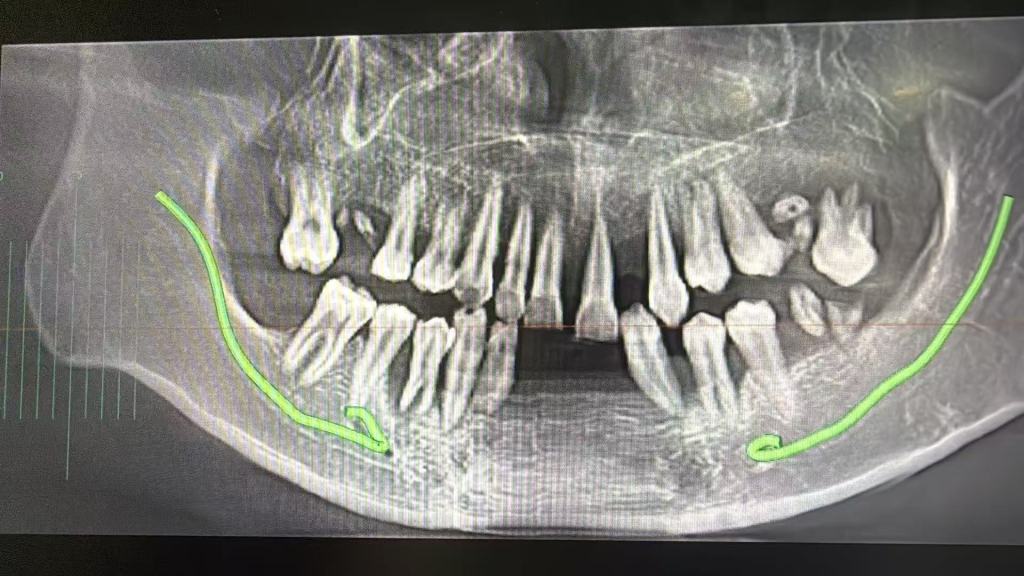

10.牙医说这是90后的小孩。。。满口松动,种植牙要20颗起步,。。好吓人,多米诺骨牌效应,爱自己,才是对家人最大的厚爱